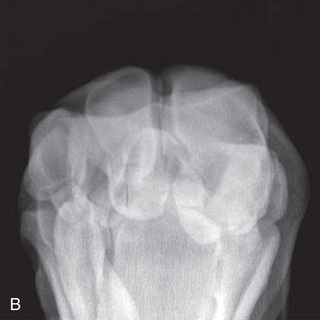

| Carpusc | DP (Standard) | -Dorsoproximal-palmarodistal (DPr-PaDi) | Weight-bearing with limbs evenly on ground and cassette on palmar aspect of limb. | Parallel to the ground, centered on palpable intercarpal joint space; slightly lateral to MSP since legs are slightly rotated externally when standing. |

Lateral (Standard) | Lateromedial extended (LM) | Weight-bearing with limbs evenly on ground and cassette against medial aspect of limb. | 90 degrees lateral to MSP; parallel to ground just distal and dorsal to prominence of accessory carpal bone. | |